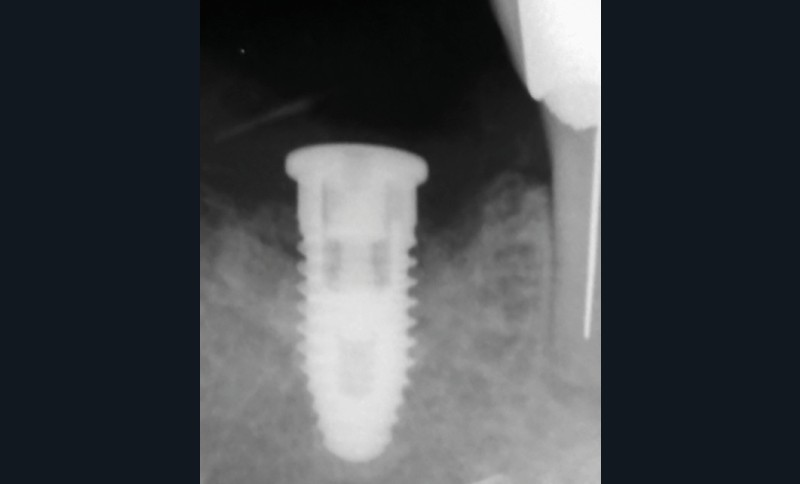

Actes préopératoires

La couronne a été déposée et une vis de couverture mise en place. La patiente a reçu un nettoyage supra-gingival général avec une attention particulière pour l’implant 47, et une irrigation locale avec du gel de chlorhexidine et du peroxyde d’hydrogène pour réduire l’inflammation des tissus. De l’amoxicilline (3 x 500 mg) a été prescrite, à commencer la veille de l’intervention chirurgicale.